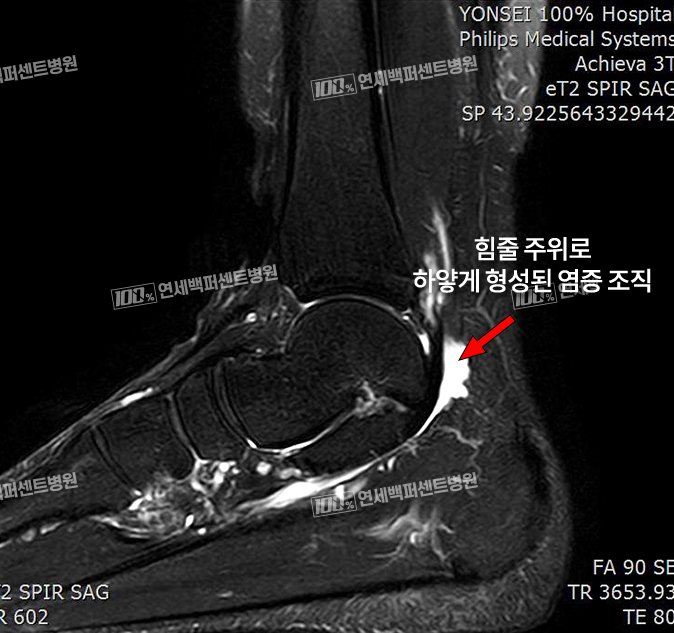

MRI 소견

후방충돌증후군(삼각골증후군)은 발목뼈 뒤쪽에 분리되어 있는 뼈조각과

그 뒤를 지나가는 힘줄이 충돌하면서 염증이 발생하는 질환!